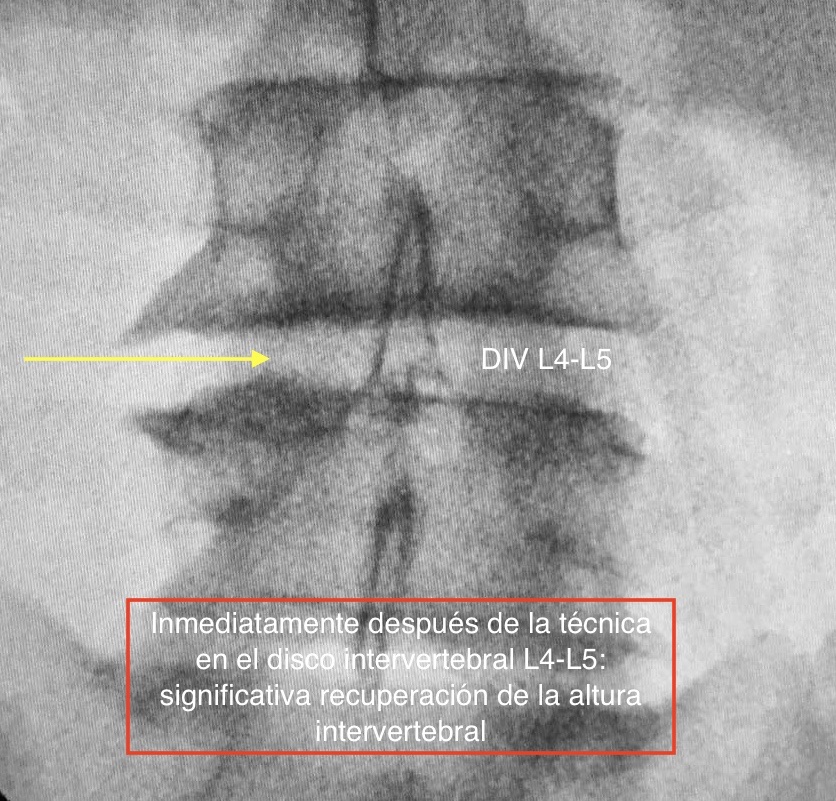

La TERAPIA REGENERATIVA NEUROESPINAL, desarrollada por el equipo de Neurocirugía de la Clínica del Remei (COT- Neurocirugía Remei) y dirigida por la Dra. Ivón González Valcárcel, es una Intervención novedosa y mínimamente invasiva exenta de reacciones adversas, avalada por evidencia científica, que utiliza la biotecnología. Nos brinda beneficios inmediatos en el control del DOLOR LUMBAR, así como ofrece efectividad en revertir la cascada degenerativa, con la consecuente REPARACIÓN y REGENERACIÓN del disco intervertebral y otros tejidos afectados.

Los factores de crecimiento plaquetarios son proteínas que se encuentran en nuestra propia sangre, ejerciendo importantes efectos biológicos. Mediante esta revolucionaria técnica, somos capaces de activarlos, concentrarlos e infiltrarlos con alta precisión en la zona dañada por la patología degenerativa. Así participarán directamente en la regulación del DOLOR y en la REGENERACIÓN, mediante la estimulación de funciones que dan lugar a la mejoría significativa o, inclusive, a la desaparición de los síntomas con rápido retorno a la actividad física cotidiana, con lo cual es una excelente alternativa a la cirugía convencional en muchos de los casos.